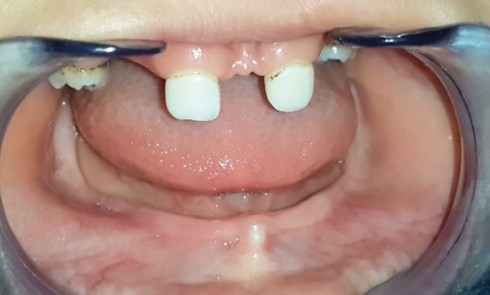

Article réservé à nos abonnés Prise en charge prothétique d’un enfant atteint d’une dysplasie ectodermique hypohidrotique

La dysplasie ectodermique est une génodermatose héréditaire liée au chromosome X qui comprend toute une série d’anomalies du développement et...